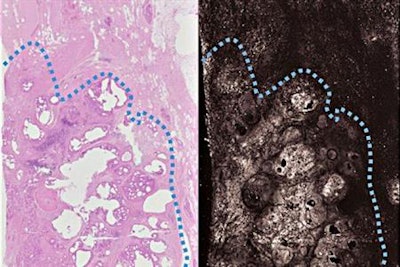

"[Our study] is a proof of concept that we can use photoacoustic imaging on breast tissue and get images that look similar to traditional staining methods without any sort of tissue processing," Novack said in a statement released by Washington University School of Medicine.